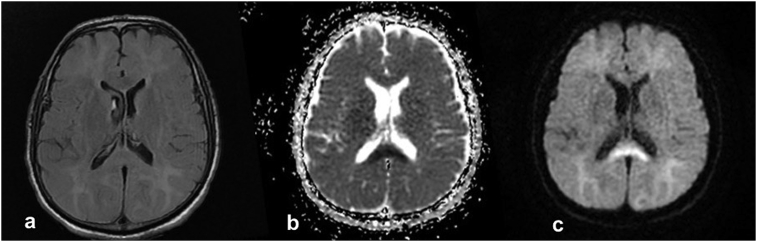

Cranial computed tomography (CT) was performed to investigate the cause of limited cooperation but revealed no acute pathological conditions. A neurology consult was scheduled to rule out acute neurological conditions. The lack of findings on cranial CT, the limited cooperation of the patient, and the changes in his consciousness resulted in a provisional diagnosis of DNS following CO exposure. Cranial MRI showed diffuse, symmetrical areas of pathological signal alterations in the deep white matter areas of both cerebral hemispheres. They were more prominent at the level of the centrum semiovale and extended to subcortical white matter areas. Those areas appeared hyperintense in T2A sequences but showed no uptake after intravenous contrast injection one-month after CO intoxication. Cranial MRI also showed areas of altered signals at the level of the body and splenium of the corpus callosum, which appeared hyperintense on diffusion-weighted imaging, and hypointense on apparent diffusion coefficient (ADC) maps. Initial imaging showed localized diffusion limitation (Fig. 1). After consultations with department of neurology, he was diagnosed with delayed central nervous system signs and symptoms secondary to CO intoxication, primarily on the basis of the patient's clinical and physical examination findings and cranial imaging signs. Hyperbaric oxygen therapy was planned and the patient was referred to a relevant medical facility.

Fig. 1.

Axial DWI MR (c) in the patient shows restricted diffusion. Correlative ADC (b) hypointensity was also demonstrated within the same geographic area (splenium of corpus callosum). Axial FLAIR MRI (a) for this patient in the ER is normal.